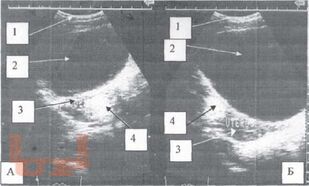

Диагностика и лечение опухолей и опухолевидных образований яичников у девочек и подростков является актуальной проблемой. Совершенство методов диагностики при данной патологии, хорошо зарекомендовавших себя во многих областях медицины, способствует внедрению их в клинику детской гинекологии, онкогематологии, детской хирургии.

Разнообразие средств диагностики, отличающихся по физическим данным и разрешающим способностям, а также по стоимости аппаратуры и самих исследований, часто ставит врача перед сложной проблемой определения необходимого минимума применяемых методов, последовательностью их выполнения и интегрирования результатов разных исследований в единую диагностическую концепцию.